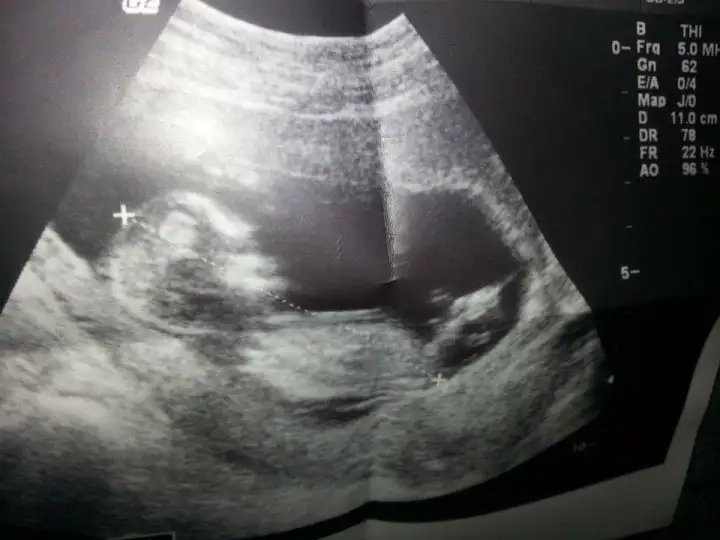

Arkadaslar, anlayan bana da bir tahmin yapabilir mı lütfen, burada 11+4 bebeğim. Ben hic anlayamıyorum Nuh teorisini ama artık cok ta merak etmeye başladım, lütfen yardım

Bende bi tahmin alabilir miyim ? :) ben bakıp bakıp göremeyen biri olarak hiç birşey anlamadım ama anlayıp yorumlayan olursa cok sevinirim :)

242,8 KB · Görüntüleme: 185

ama o nub mudur nedir seninkinde bariz görünyo ben bile gördüm yani